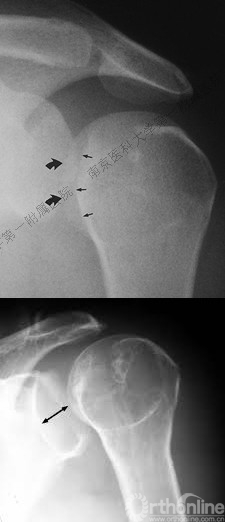

五、反Hill-Sachs 损伤对肩关节稳定性的影响

1.反Hill-Sachs损伤范围对肩关节后方稳定性具有决定性的影响。

2.常规的影像学测量方法不能准确反映损伤范围。

六、肩胛盂及韧带复合体损伤对肩关节后向稳定性的影响

1.肩胛盂后侧可以因骨折导致缺损(反Bankart损伤),或发生盂肱韧带附着处的撕脱骨折。

盂肱下韧带肱骨侧止点撕裂

3.反Hill-Sachs损伤合并反Bankart损伤被Moroder命名为“双极损伤”。

4.δ角是发生肱骨头后脱位所需的肩关节内旋角度,在双极损伤中δ角减小,所以在双极损伤中,即使较轻的反Hill-Sachs损伤也需要修复。